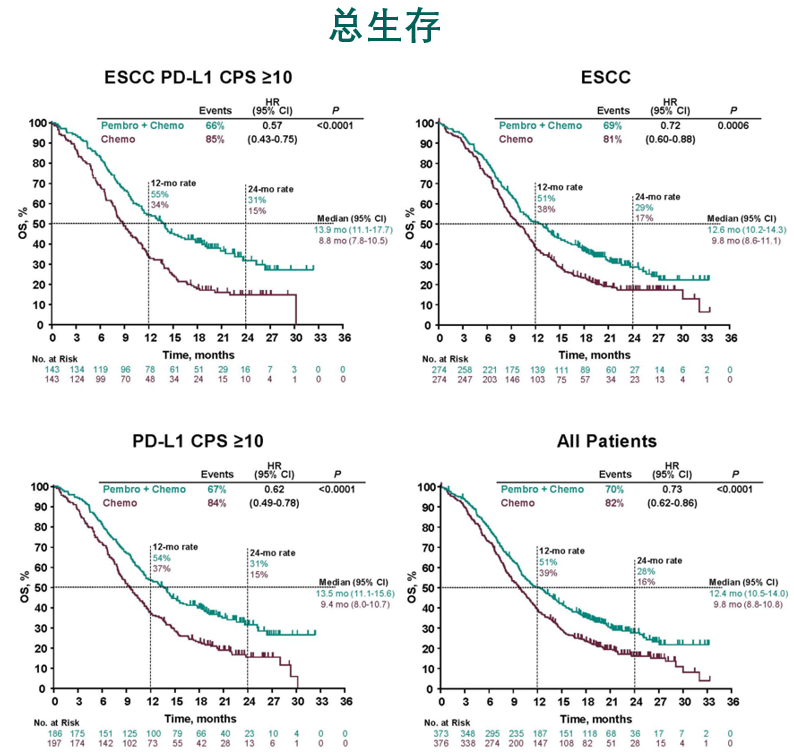

今日(2021年4月24日),中国临床肿瘤学会(CSCO)发布《2021年版食管癌诊疗指南》(以下简称“CSCO指南”),首次推荐PD-1免疫检查点抑制剂用于晚期...

2020年的金秋,欧洲肿瘤内科学会(ESMO)年会如期而至,免疫治疗在消化系统肿瘤的治疗中大放异彩。其中食管癌领域最重磅级研究——Keynote-590研究在...